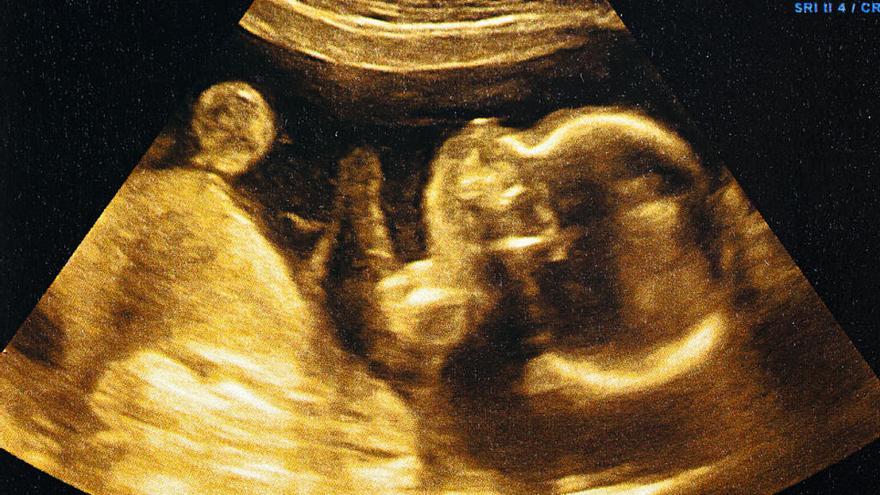

Emma es el nombre de la niña que fue concebida en Tennessee desde un embrión almacenado en octubre de 1992, hace un cuarto de siglo, un año y medio después de que naciera su madre, Tina Gibson.

La madre incidió en que estaba muy "agradecida" y calificó a su hija, que pesó algo más de tres kilos y midió 50 centímetros de altura, como un "precioso regalo de Navidad".

Tina Gibson quedó embarazada el pasado marzo después de que el embrión fuese transferido a su útero.